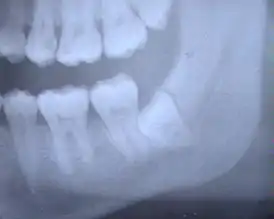

Перикоронит (перикоронарит) — воспаление мягких тканей десны, окружающих прорезающийся или прорезавшийся зуб.

Перикоронит часто встречается при прорезывании зубов мудрости, когда зуб остаётся частично непрорезавшимся.